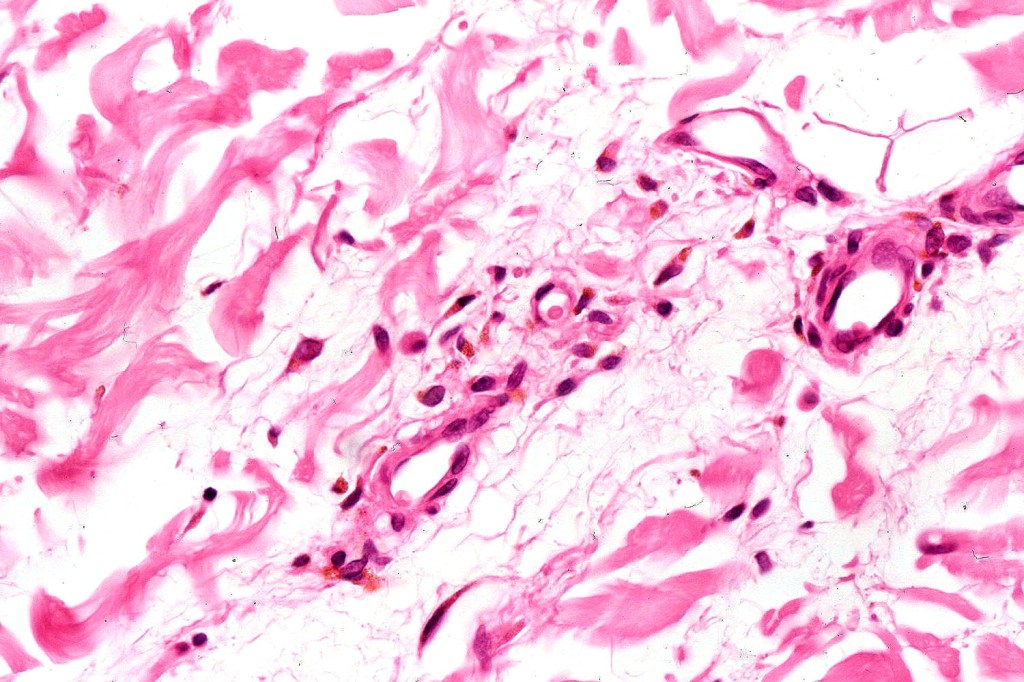

•Admixture of spindle cells, pigmented bipolar or dendritic cells & melanophages

•Cytoplasm is pale and nuclei are small with inconspicuous nucleoli

•Multinucleate giant cells sometimes present

•Stromal fibrosis, myxoid change, vascular hyalinization with cyst formation are often seen

•Perineural involvement may be seen